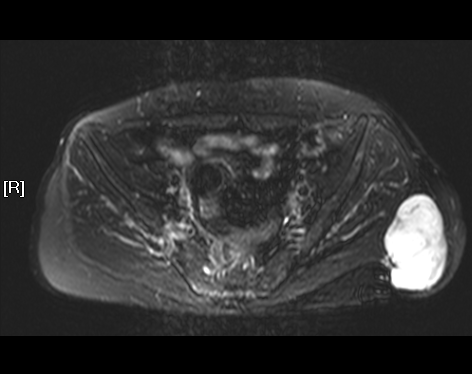

TWI 2 压脂